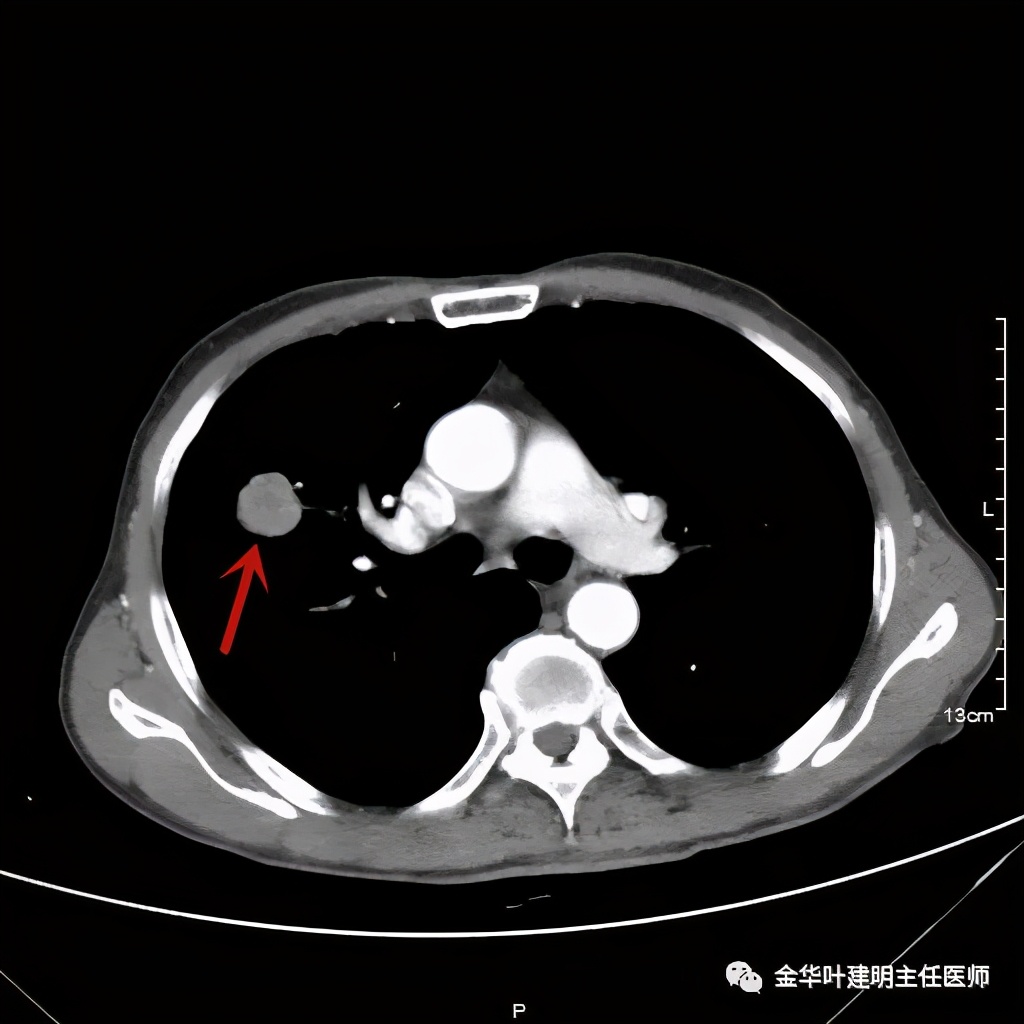

上图桔色箭头示血管进入病灶,较粗;紫色箭头示病灶与胸膜间似乎有所牵拉;红色箭头示病灶

上图桔色箭头示血管进入;红色箭头示病灶

上图示病灶边缘不太光整,内部密度不太均匀

上图紫色箭头示叶间胸膜受牵拉,病灶边缘部分见到细毛刺